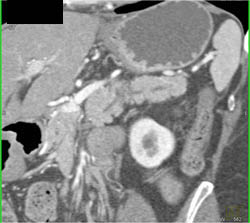

Collaterals Due to Splenic Vein Occlusion Due to Pancreatic Cancer